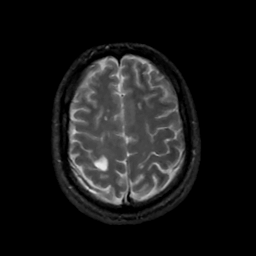

MR Study #12, May 12, 1991 -- Slice #39